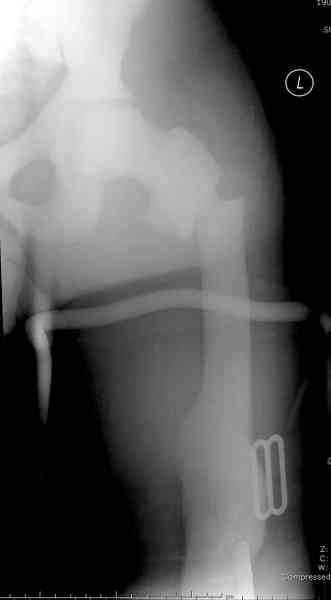

Что-то пациенту как-то не везет по жизни... Тоже самое - интрамедуллярный остеосинтез коротким штифтом для проксимального отдела бедра. Ранняя нагрузка сразу...

После неудачной попытки скелетного вытяжения в первом мед.учреждении, после осмотра снимков и изучения истории, поставили диагноз “Остеопетроз” или мраморная болезнь, редкая наследственная костная паталогия, где имеется нарушение формации остеокластов.

Конечно, было бы идеальным применение интрамедуллярного остеосинтеза, но учитывая прежний собственный опыт (лечил перелом бедра) и

публикации, предупреждающие о трудностях при обработке кости (иногда из-за неподготовленности инструментария результатом была неадекватная фиксация перелома, или перенос операции из-за фактора усталости оперирующего персонала), решили применить пластину (и в этом же случае был выбран Synthes plate, так что представитель за два дня

зароботал... на десерт тоже).

Заказаны были дополнительные различные дрели, и на следующий день, усиленной бригадой, больного прооперировали, потратив на каждое отверстие около 25-35 минут, хотя сверлили с охлаждением по нарастающей по диаметру сверл и с их заменой каждые 2 мм сверления.